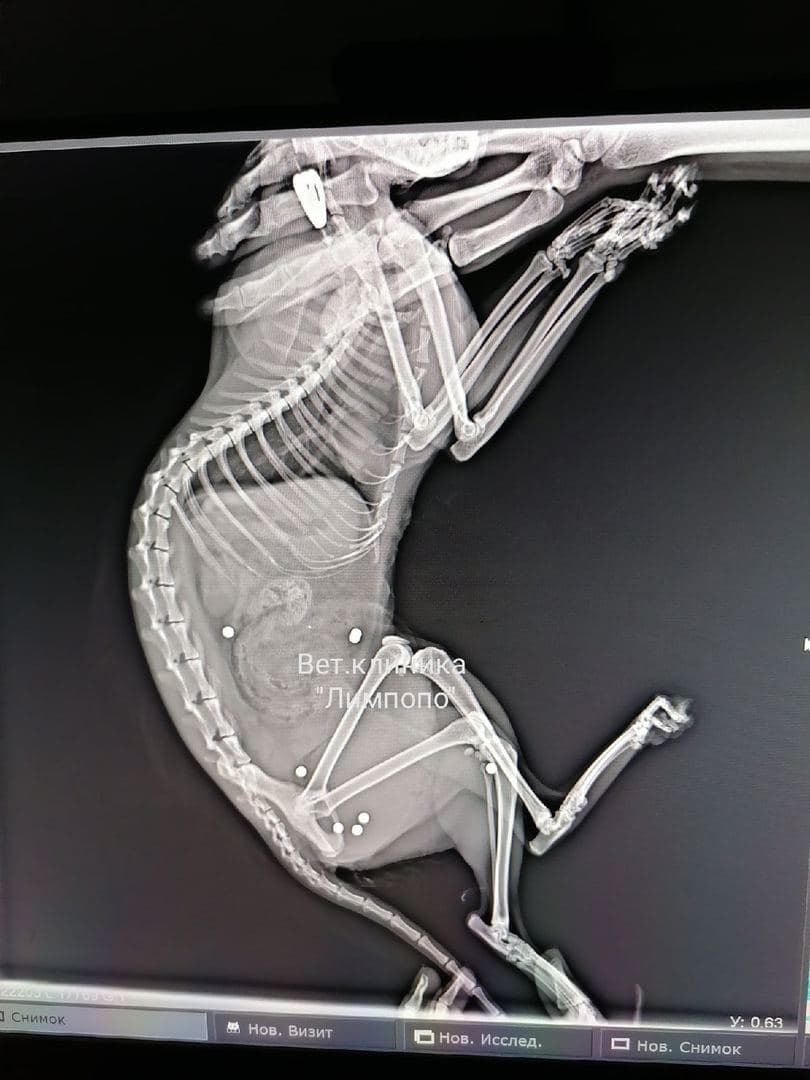

Полиция начала проверку после попадания в красноярскую ветклинику кошки с семью пулевыми ранениями

Как рассказали сотрудники клиники «Липмопо», 7 пулевых ранений у животного выявились на рентгене. После ранения кошка выжила, но сильно пострадала.

Полицейские предполагают, что в кошку стреляли из пневматики. В самой клинике произошедшее пока не комментируют.